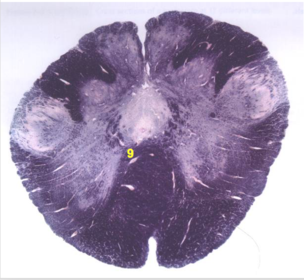

| Spinal tract of V | |

| Spinal nucleus of V | |

| Medial vestibular nucleus | |

| Inferior vestibular nucleus | |

| Dorsal cochlear nucleus | |

| Ventral cochlear nucleus | |

| Inferior olivary complex | |

| Inferior cerebellar peduncle | |

| CN IX | |

| Anterior spinocerebellar tract | |

| Central tegmental tract | |

| Olivary internal arcuate fibers | |

| Solitary tract | |

| Abducens root fibers | |

| Longitudinal pontine fibers (corticospinal tract) | |

| Transverse pontine fibers (dark fibers) | |

| Pontine nuclei (pale) | |

| Medial lemniscus | |

| ALS | |

| Trapezoid body | |

| Ventral trigeminothalamic tract | |

| Superior olive | |

| Facial nerve root fibers - descending | |

| Facial motor nucleus | |

| Interposed nuclei | |

| Medial longitudinal fasciculus | |

| Facial nerve root - internal genu | |

| Abducens nucleus | |

| Lateral vestibular nucleus | |

| Superior vestibular nucleus | |